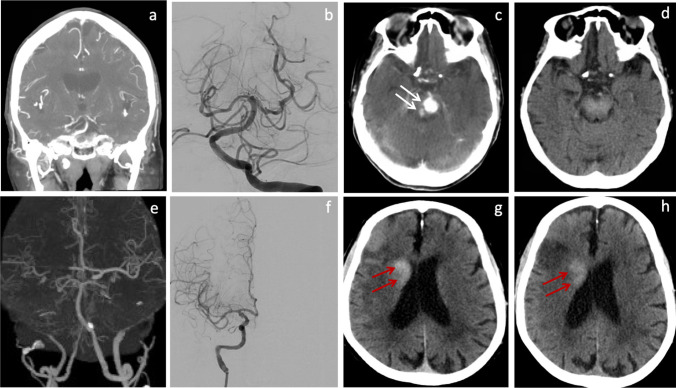

Non-contrast CT scans were performed immediately and 24–36 h after MT in study patients. CE was defined as hyperdense lesion on the immediate post-MT CT but not on the 24–36-h follow-up scans. Persistent or new hyperdense lesion on 24–36-h follow-up CT was classified as ICH. In patients with follow-up MRI study, ICH was determined using susceptibility-weighted imaging (SWI). ICH includes intracerebral hemorrhage, subarachnoid hemorrhage (SAH), or subdural hemorrhage (SDH). Symptomatic ICH (sICH) was defined as evidence of ICH on CT scan and a neurologic deterioration with an increase in NIHSS score by more than 4 points [8]. Asymptomatic ICH (aICH) was defined as evidence of ICH on CT scan without significant neurologic deterioration. The representative images of the CE and ICH are shown in Fig. 2.

Fig. 2.

Upper panel: contrast extravasation (white arrow). A 75-year-old patient presented with drowsiness and speech difficulty. CTA showed distal BA occlusion (a). Immediately after endovascular recanalization (b), CT scan showed hyperdense lesions in the pons (c), which resolved on follow-up CT scan 24 h later (d). Lower panel: ICH (red arrows). A 74-year-old patient presented with slurred speech and left-sided weakness. CTA sowed right carotid terminus and MCA occlusion (e). Immediately after endovascular recanalization (f), CT scan showed hyperdense lesion in the right basal ganglia (g), which persisted on follow-up CT scan 24 h later (h)